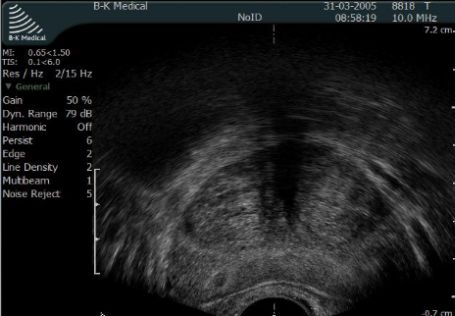

Zwapnienia w gruczole krokowym są często opisywane przez radiologów wykonujących badanie USG jamy brzusznej. Ocena echogeniczności gruczołu krokowego w badaniu wykonywanym głowicą convexową (głowica służąca do badań ultrasonograficznych jamy brzusznej) jest niemiarodajna i nie wnosi nic do diagnostyki. Wielokrotnie u młodych, bezobjawowych mężczyzn obserwuje się hiperechogenne odbicia w obrębie gruczołu krokowego, które mogą być mylnie interpretowane jako zwapnienia.

Fot. Przekrój poprzeczny gruczołu krokowego - obraz w transrektalnym USG.